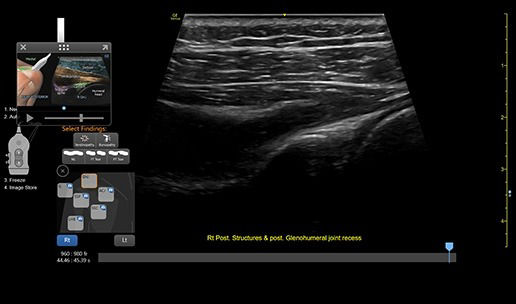

VENUE COACH MSK

Simplifying MSK scans

This easy-to-use exam documentation tool assists users through exams by providing reference images and anatomy markups. Multiple anatomical areas and helpful video tutorials help clinicians to acquire the scans they need.

• MSK Diagrams: Simplifies documentation and assists the clinician in follow up for patients. No need to manually type findings—you can simply assign a label from a pre-populated list that correlates with the images. Get a single view diagram with one click image storing, keep track of assessments and show trends in response to therapy.

• Reference Image: Reference image provides anatomy mark-ups to assist novice users in scanning the correct anatomy

• Bilateral mode: Helps you to view the opposite side of the same zone for comparison (available for Shoulder preset)